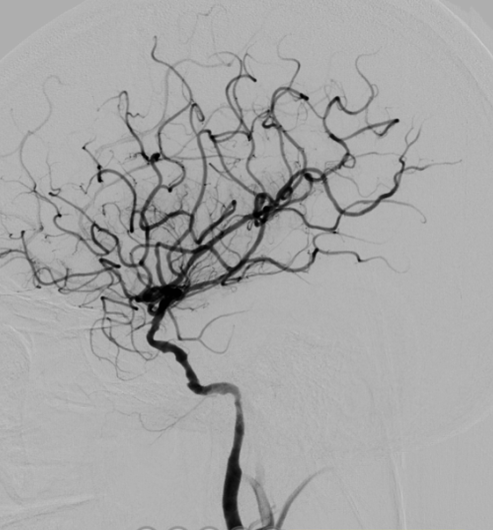

术后影像及检查

术后造影。

导丝怎么扩【载药时代 球扩天下】NOVA DES®颅内药物洗脱支架在颈内动脉颅内段重度狭窄的应用二例!_https://www.jmylbn.com_新闻资讯_第33张